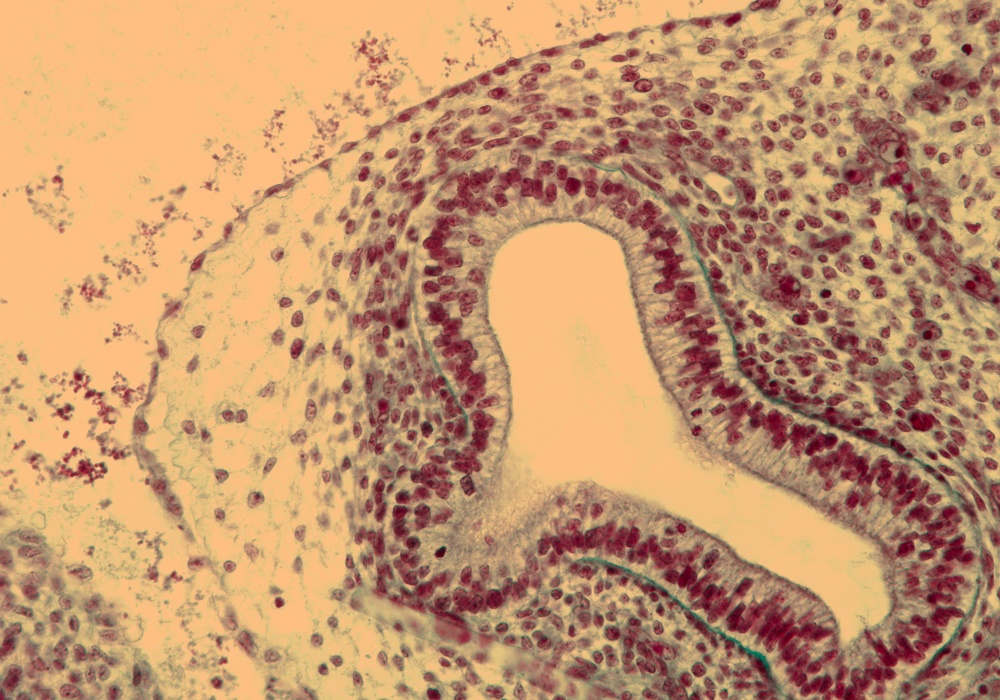

Tissue

–

Peripheral Bronchus in Rt. Lung

Carnegie Embryo #9226

Location:

121-01-01